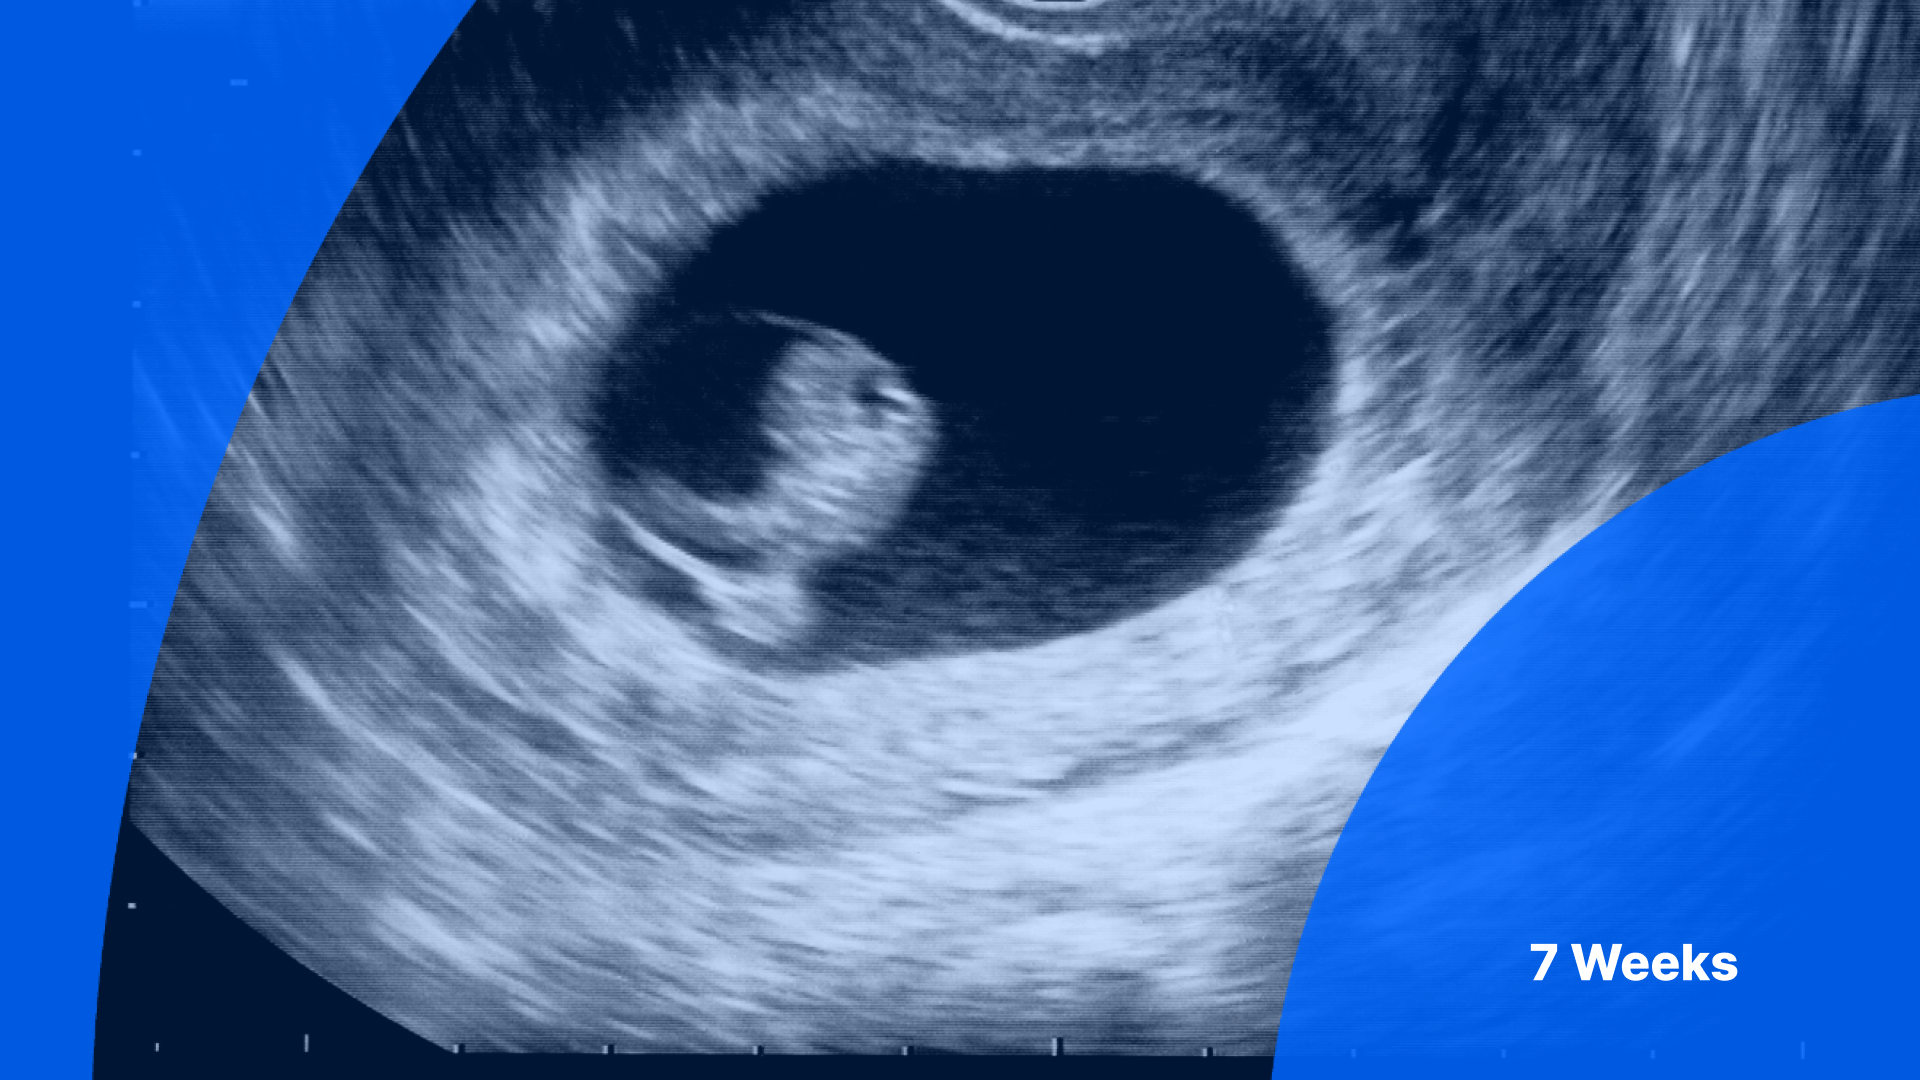

7 Weeks Pregnant Ultrasound | PocketHealth

www.pockethealth.comHow Does Dating Ultrasound Work – Telegraph

www.pockethealth.comHow Does Dating Ultrasound Work – Telegraph